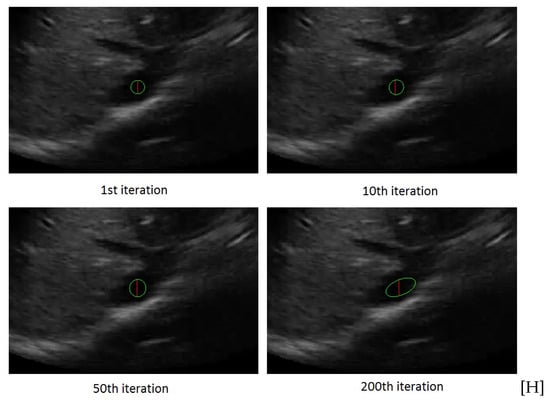

Figure 2 shows the ellipse evolution versus the number of iterations for a sample IVC frame.

Figure 2.

The rectangle evolution versus number of iterations.

Figure 4 shows the rectangle evolution versus number of iterations for the IVC image as in Figure 2. By comparison of Figure 2 and Figure 4, one can see the active rectangle algorithm not only converges faster but also more accurately estimates the AP-diameter than the active ellipse algorithm.

Figure 4.